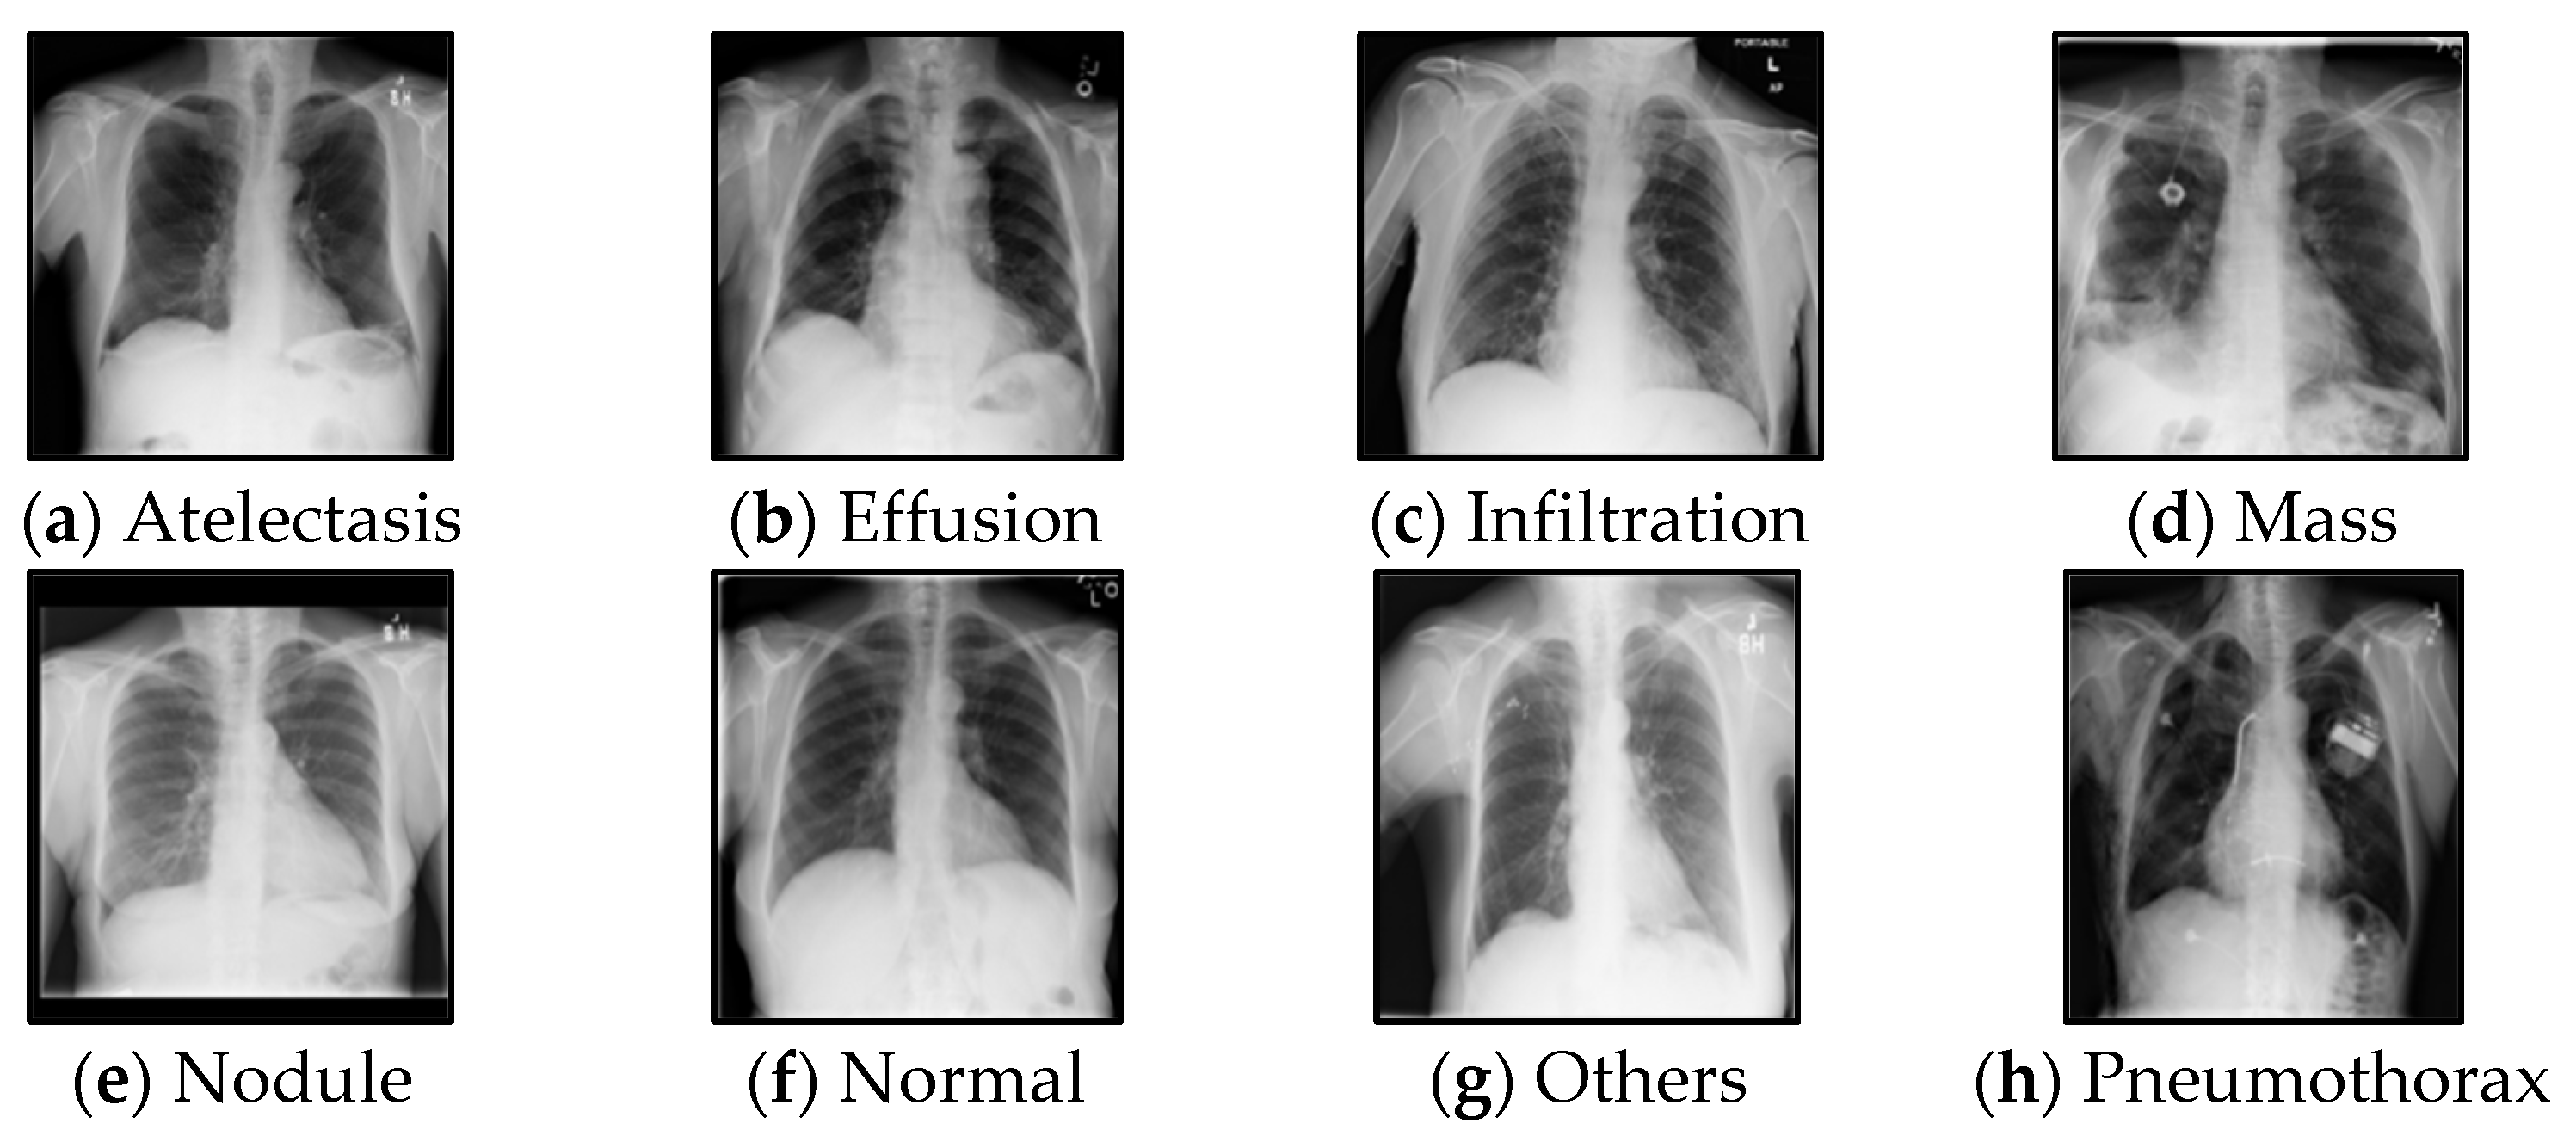

3.1. Chest X-ray Pseudo-Labelling Results

| Atelectasis | 79.4 | 81.97 | 94.0 |

| Nodule | 75.2 | 77.38 | 96.0 |

| Mass | 88.4 | 85.32 | 84.0 |

| Effusion | 88.2 | 82.75 | 91.0 |

| Infiltration | 70.5 | 71.62 | 86.0 |

| Pneumothorax | 87.8 | 83.41 | 93.0 |